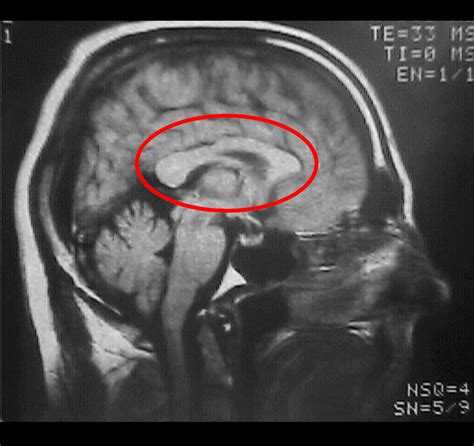

Corpus Callosum Agenesis is a congenital condition, meaning it is present at birth. It can occur as an isolated condition or as part of a broader syndrome. The severity of symptoms can vary widely among individuals, ranging from mild to severe. The condition is often diagnosed through imaging techniques such as magnetic resonance imaging (MRI), which can clearly visualize the absence or underdevelopment of the corpus callosum.

Diagnosis typically involves a combination of clinical evaluation and imaging studies. MRI is the gold standard for diagnosing Corpus Callosum Agenesis, as it provides detailed images of the brain’s structure. Additional tests, such as electroencephalography (EEG) for seizure monitoring and genetic testing, may also be conducted to identify underlying causes and associated conditions.

• Neuroimaging Techniques: Developing advanced imaging techniques to better visualize and understand brain structure and function in individuals with Corpus Callosum Agenesis.

• corpus callosum agenesis mri